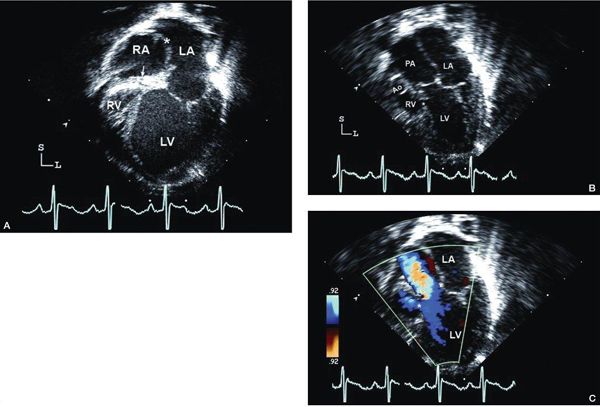

Figure 12.2. Tricuspid atresia with normally related great arteries; subcostal views. A: “Four-chamber” (coronal) view showing moderate-sized secundum atrial septal defect (asterisk), atretic tricuspid valve (arrow), hypoplastic right ventricle (RV), and dilated left ventricle (LV). B: Four-chamber view, angled anteriorly, illustrating the large ventricular septal defect (asterisk). Aortic (Ao) origin from LV in normally related great arteries. C: Short-axis (sagittal) view showing anterior RV, posterior LV, and muscular ventricular septal defect (asterisk). In normally related great arteries, the pulmonary artery (PA) arises anteriorly from the RV and bifurcates early. LA, left atrium; RA, right atrium (Video 12.1).

Figure 12.3. Tricuspid atresia with transposed great arteries; subcostal long-axis (coronal) views. A: Dilated left ventricle (LV), hypoplastic right ventricle (RV), and a small muscular ventricular septal defect (asterisk). Note the pulmonary artery (PA) arising from the LV with early bifurcation (arrowhead). B: Color Doppler imaging in the same patient demonstrating flow in the PA bifurcation (arrow). C: Slight anterior angulation of the transducer demonstrates the LV, hypoplastic RV, and the restrictive ventricular septal defect (asterisk). The anterior aorta (Ao) arises from the hypoplastic RV. D: Color Doppler demonstrating the flow across the small ventricular septal defect (arrow), antegrade into the aorta (Video 12.2).